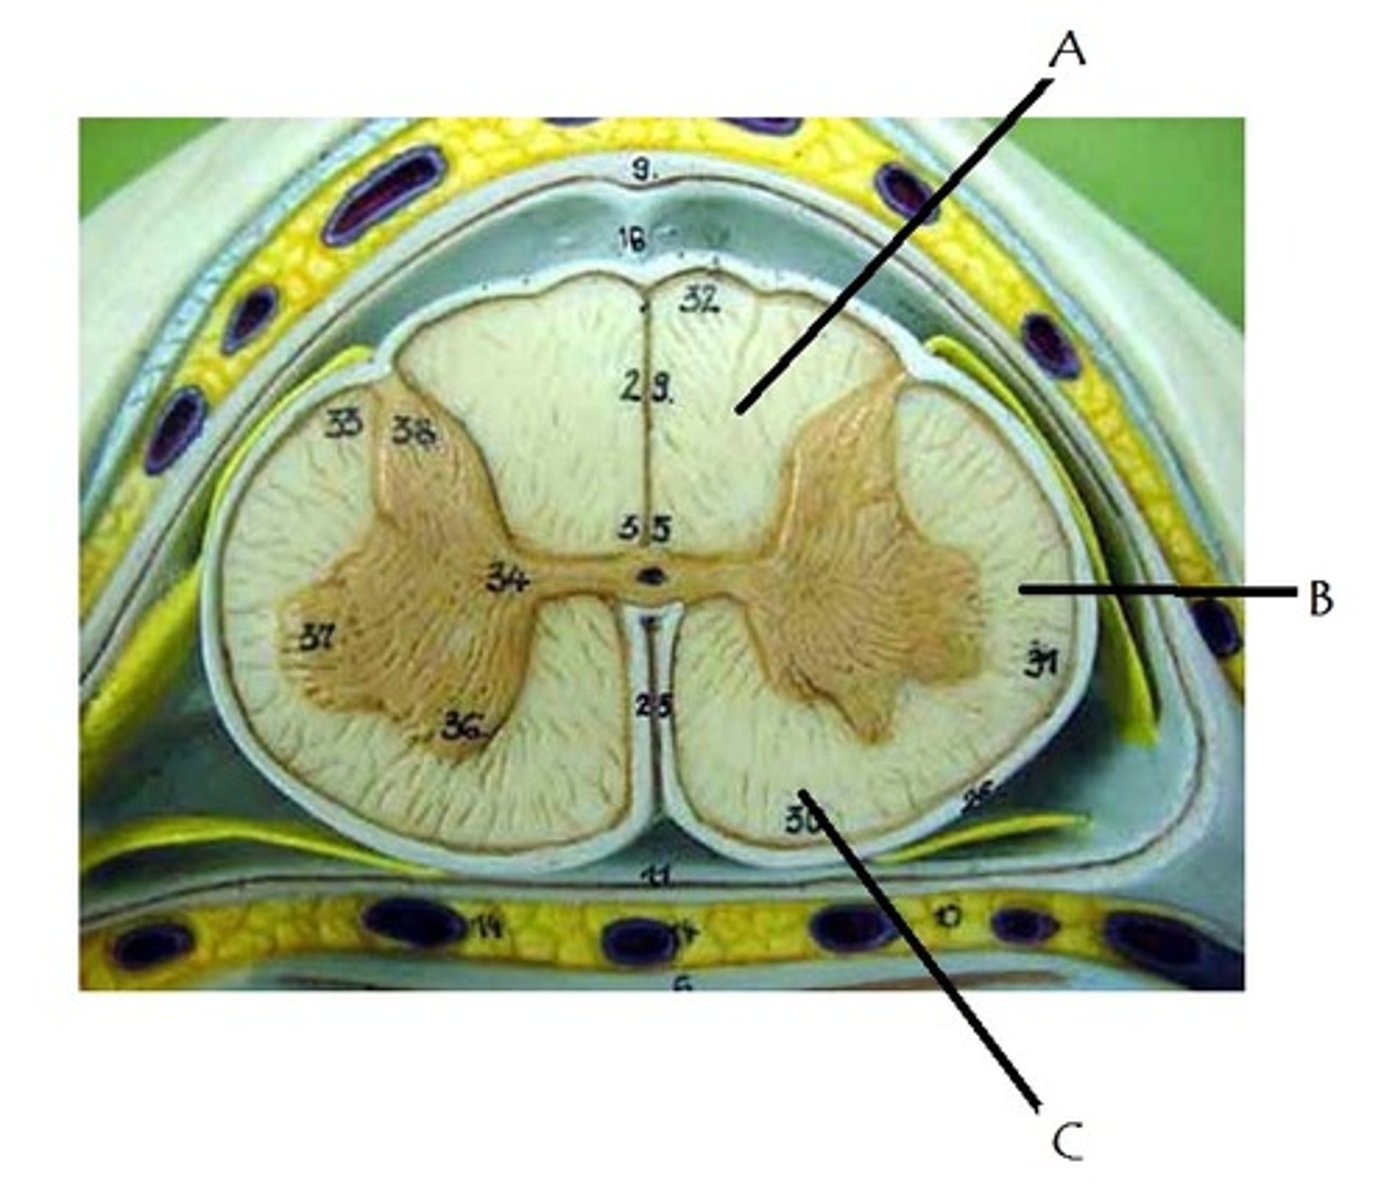

posterior median sulcus

anterior median fissure

posterior white column

A

anterior white column

C

lateral white column

B

posterior gray horn

anterior gray horn

lateral gray horn

gray commissure

Part of grey matter connecting the two halves of the grey matter in spinal cord

central canal

Hole in the center

Name this passageway

epidural space

dura mater

thick, outermost layer of the meninges surrounding and protecting the brain and spinal cord

subdural space

space between dura mater and arachnoid mater

arachnoid mater

middle layer of the meninges

B on model

subarachnoid space

a space in the meninges beneath the arachnoid membrane and above the pia mater that contains the cerebrospinal fluid

pia mater

the delicate innermost membrane enveloping the brain and spinal cord.

denticulate ligaments

extensions of pia mater that secure cord to dura mater laterally